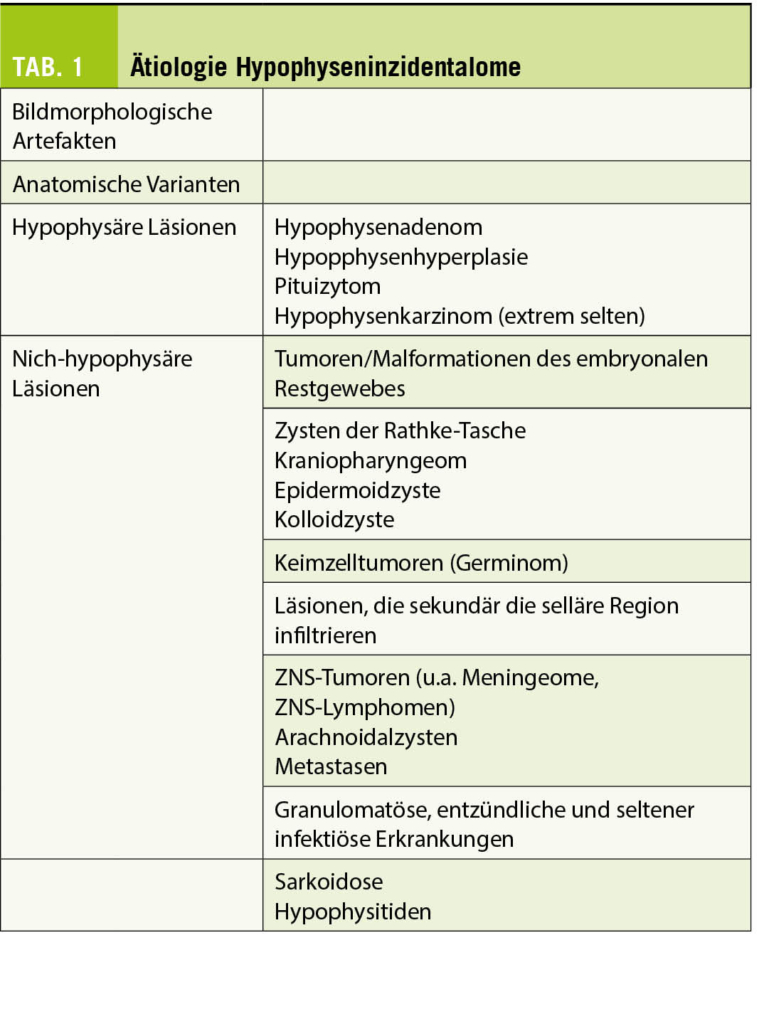

Die Ätiologie der Läsion ist vielfaltig (Tab. 1) (1, 3, 4). Nicht so selten handelt sich bei den Läsionen um bildtechnischen Artefakten ohne morphologischen Korrelat, sowie um anatomischen oder physiologischen (z.B. Zyklusabhängig bei Frauen) Varianten ohne pathologischer Bedeutung.